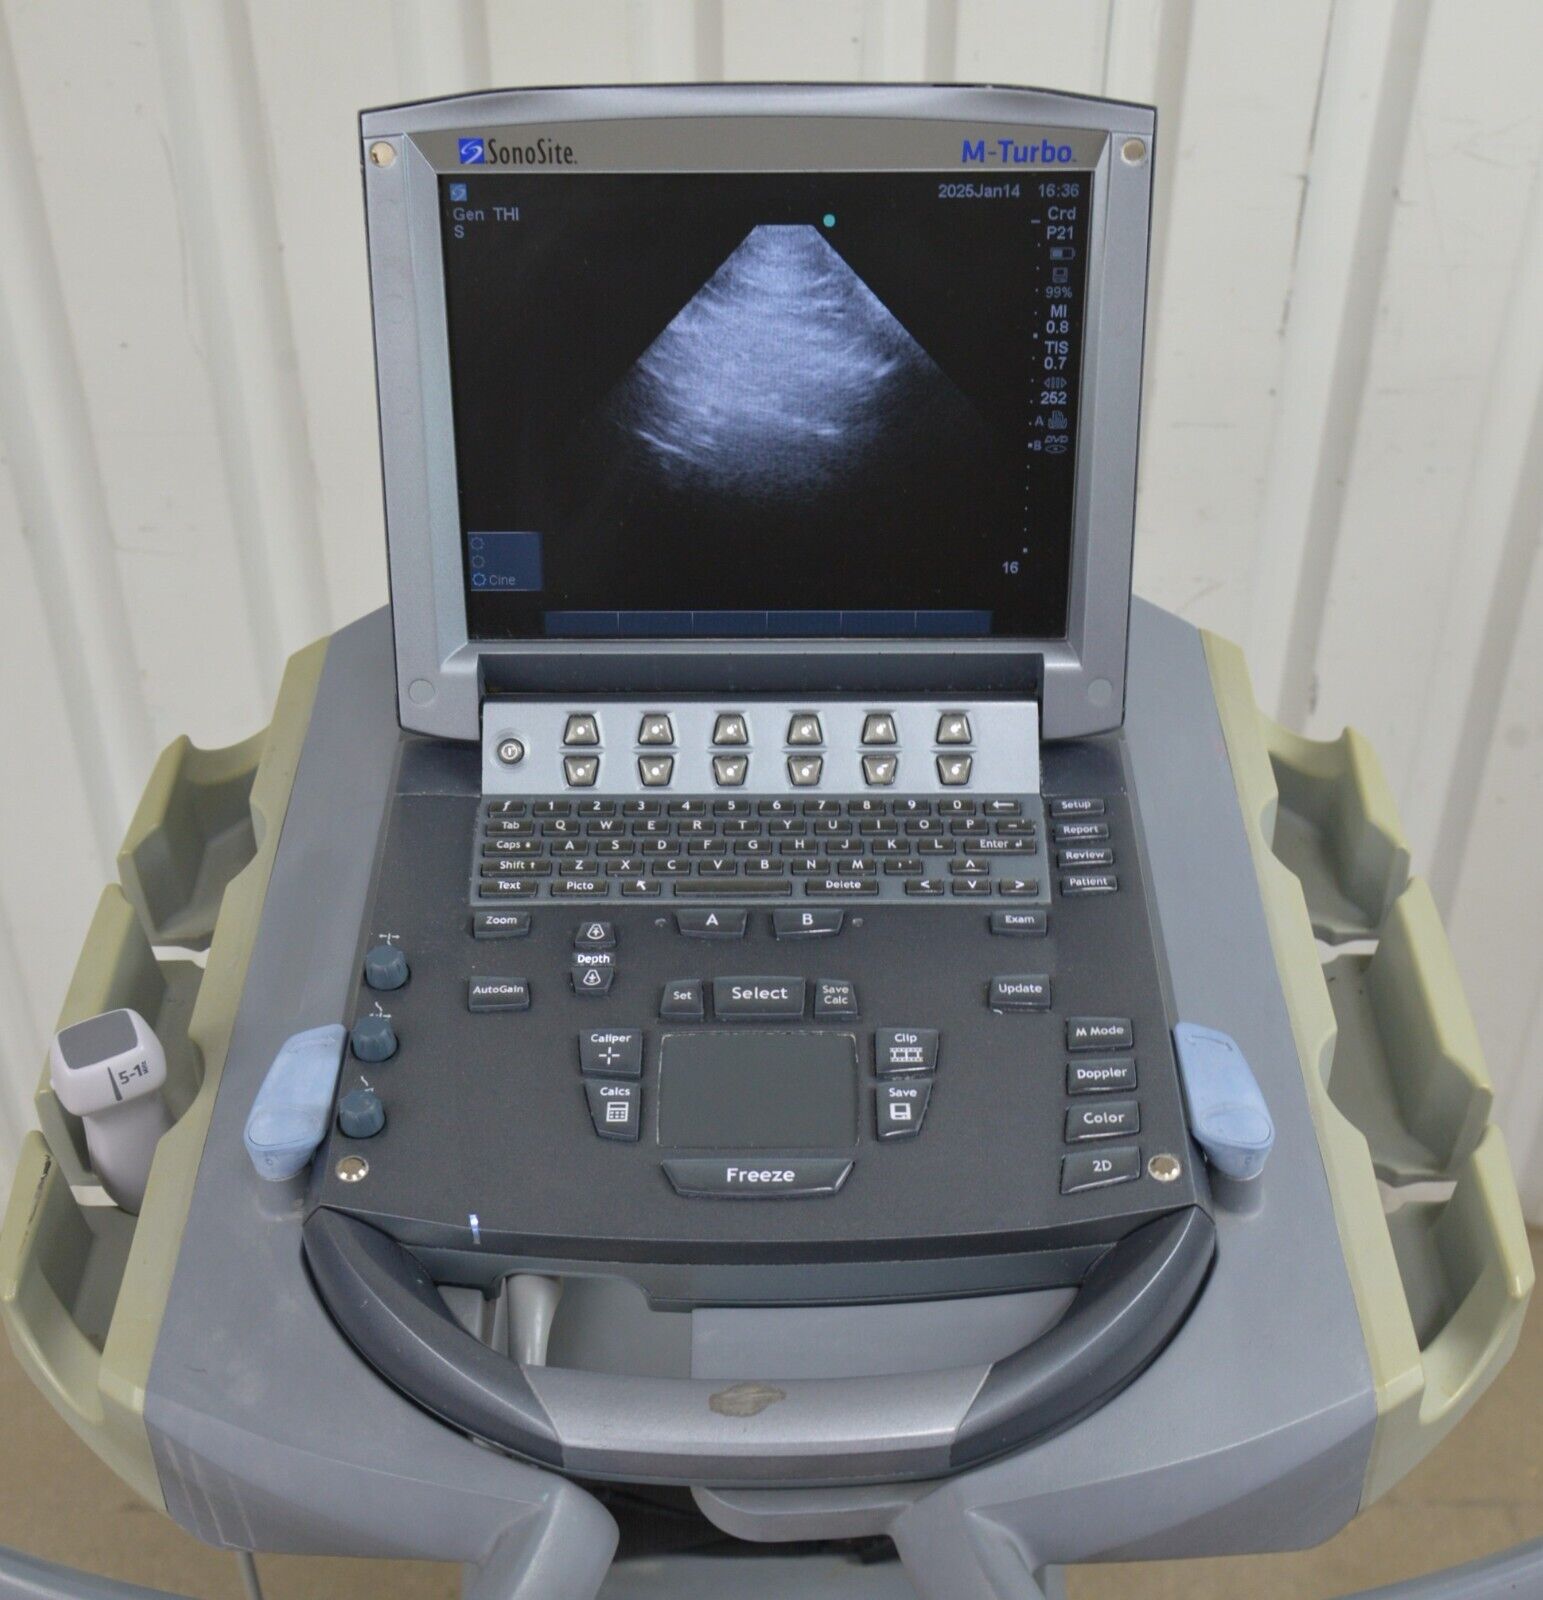

- Fujifilm Sonosite M-Turbo Ultrasound System W/ SonoSite P21x/5-1 MHz Transducer

January 15, 2025Fujifilm Sonosite M-Turbo Ultrasound System W/ SonoSite P21x/5-1 MHz Transducer

Fujifilm Sonosite M-Turbo Ultrasound System W/ SonoSite P21x/5-1 MHz Transducer

This Fujifilm Sonosite M-Turbo Ultrasound System W/ SonoSite P21x/5-1 MHz Transducer is in good working condition. This unit powers on properly and the display screen produces a clear picture. The buttons respond properly to selection and the connections are clean and in good condition. The battery holds a charge. There are a few minor scuff marks from previous use (see photos). This item comes with a 30 day satisfaction guarantee. Includes everything displayed in the photos and nothing else.